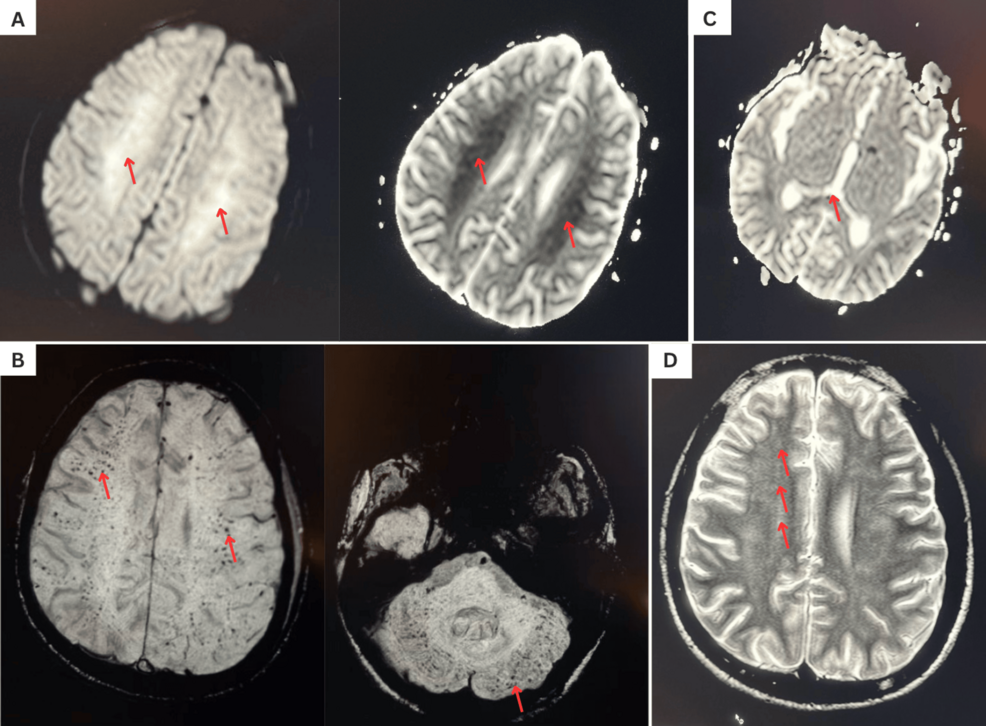

Diagnosing FES can be challenging, as its symptoms – including respiratory distress, neurological changes, and a characteristic skin rash – can mimic other conditions. The case report emphasizes the importance of a high index of suspicion in SCD patients presenting with these symptoms, particularly following a vaso-occlusive crisis. Diagnostic tools, such as imaging modalities, play a crucial role in differentiating FES from other potential causes of similar symptoms. A recent literature review details the various imaging modalities used to distinguish between bone infarction and osteomyelitis in SCD, aiding in accurate diagnosis.